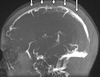

1

Q

A

quadrigeminal cistern